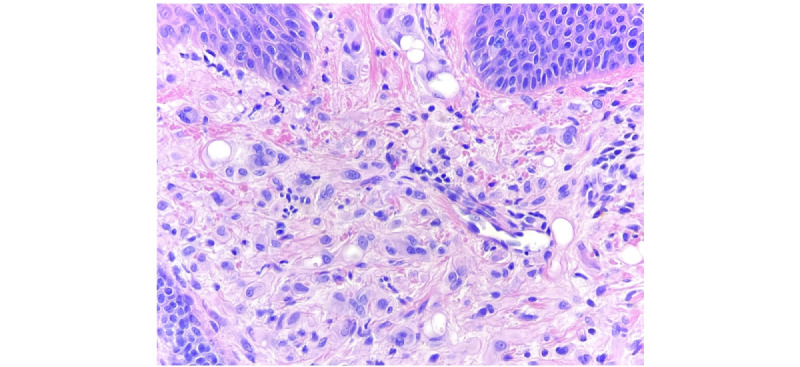

Epithelioid hemangioendothelioma (EHE) is a rare vascular tumor with metastatic potential. EHE can have single- or multiorgan involvement, with presentations ranging from asymptomatic disease to pain and systemic symptoms. The extremely heterogeneous clinical presentation and disease progression complicates EHE diagnosis and management. We present the case of a 24-year-old woman with two periauricular erythematous papules, leading to the discovery of metastatic EHE through routine biopsy, despite a noncontributory medical history. Histology revealed the dermal proliferation of epithelioid cells and vacuoles containing red blood cells. Immunohistochemistry markers consistent with EHE solidified the diagnosis. Although extremely rare, prompt diagnosis of EHE is essential for informed decision-making and favorable outcomes. Key clinical and histopathological findings are highlighted to aid dermatologists in diagnosing and managing this uncommon condition.

上皮样血管内皮瘤(EHE)是一种罕见的血管肿瘤,具有转移潜力。EHE可累及单个或多个器官,表现为无症状、疼痛和全身症状。临床表现和疾病进展的异质性极高,使 EHE 的诊断和治疗变得复杂。我们介绍了一例 24 岁女性的病例,她有两个耳周红斑丘疹,尽管病史不详,但通过常规活检发现了转移性 EHE。组织学检查发现真皮层增生的上皮样细胞和含有红细胞的空泡。与 EHE 一致的免疫组化标记物明确了诊断。尽管 EHE 极其罕见,但及时诊断对于做出明智决策和取得良好疗效至关重要。本文强调了关键的临床和组织病理学发现,以帮助皮肤科医生诊断和处理这种不常见的疾病。